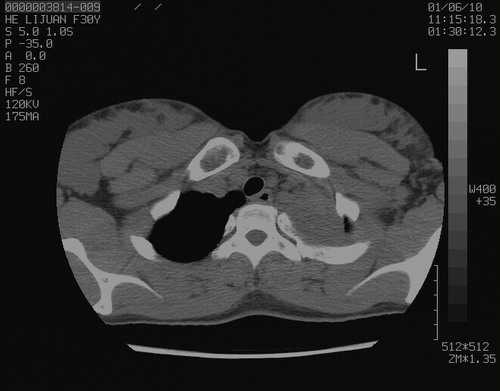

怀孕3个月时(2009-3至4月间),自述突感左侧前后胸疼痛1天,以前胸明显,随后偶感闷痛,余未见异

左肺尖脊柱旁沟肿块,境界清楚,边缘光滑,密度不均,内有多发点片状钙化,考虑良性肿瘤,骨软骨瘤或神经源性肿瘤可能,肺错构瘤不除外。

左后上纵隔见一类圆形肿块影,外侧边界清,密度不均匀,内可见点状钙化影,增强呈不均匀强化,考虑神经源性肿瘤可能。期待病理结果。